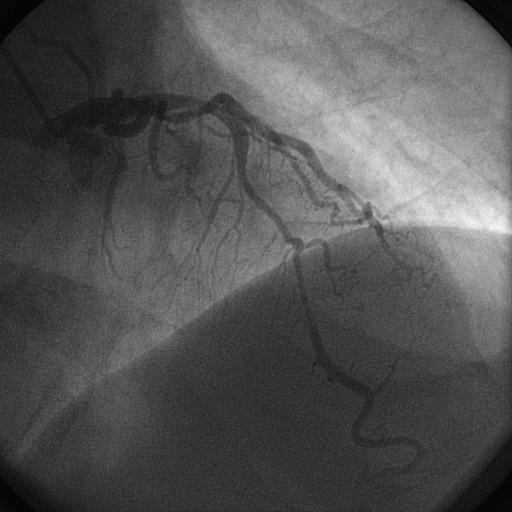

La cinecoronariografía o angiografía coronaria todavía es considerada el método de imagen padrón oro (gold standar) para la valoración de la anatomía coronaria. Desde la primera angioplastía coronaria…

A cinecoronariografia ou angiografia coronariana ainda é considerada o método de imagem padrão-ouro para avaliação da anatomia coronariana. Desde a primeira angioplastia coronariana realizada, a angio…